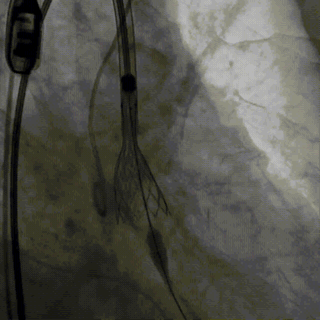

术中先行冠脉造影检查,前降支中段有明显狭窄,随即先行PCI治疗,植入冠脉支架。

主动脉根部造影,显示瓣叶增厚,伴有明显返流。

选择22mm球囊进行预扩,结果显示具有明显腰征,无瓣周返流,随即选择TaurusElite26mm瓣膜,凭借其优异的柔顺性,轻松完成过弓。